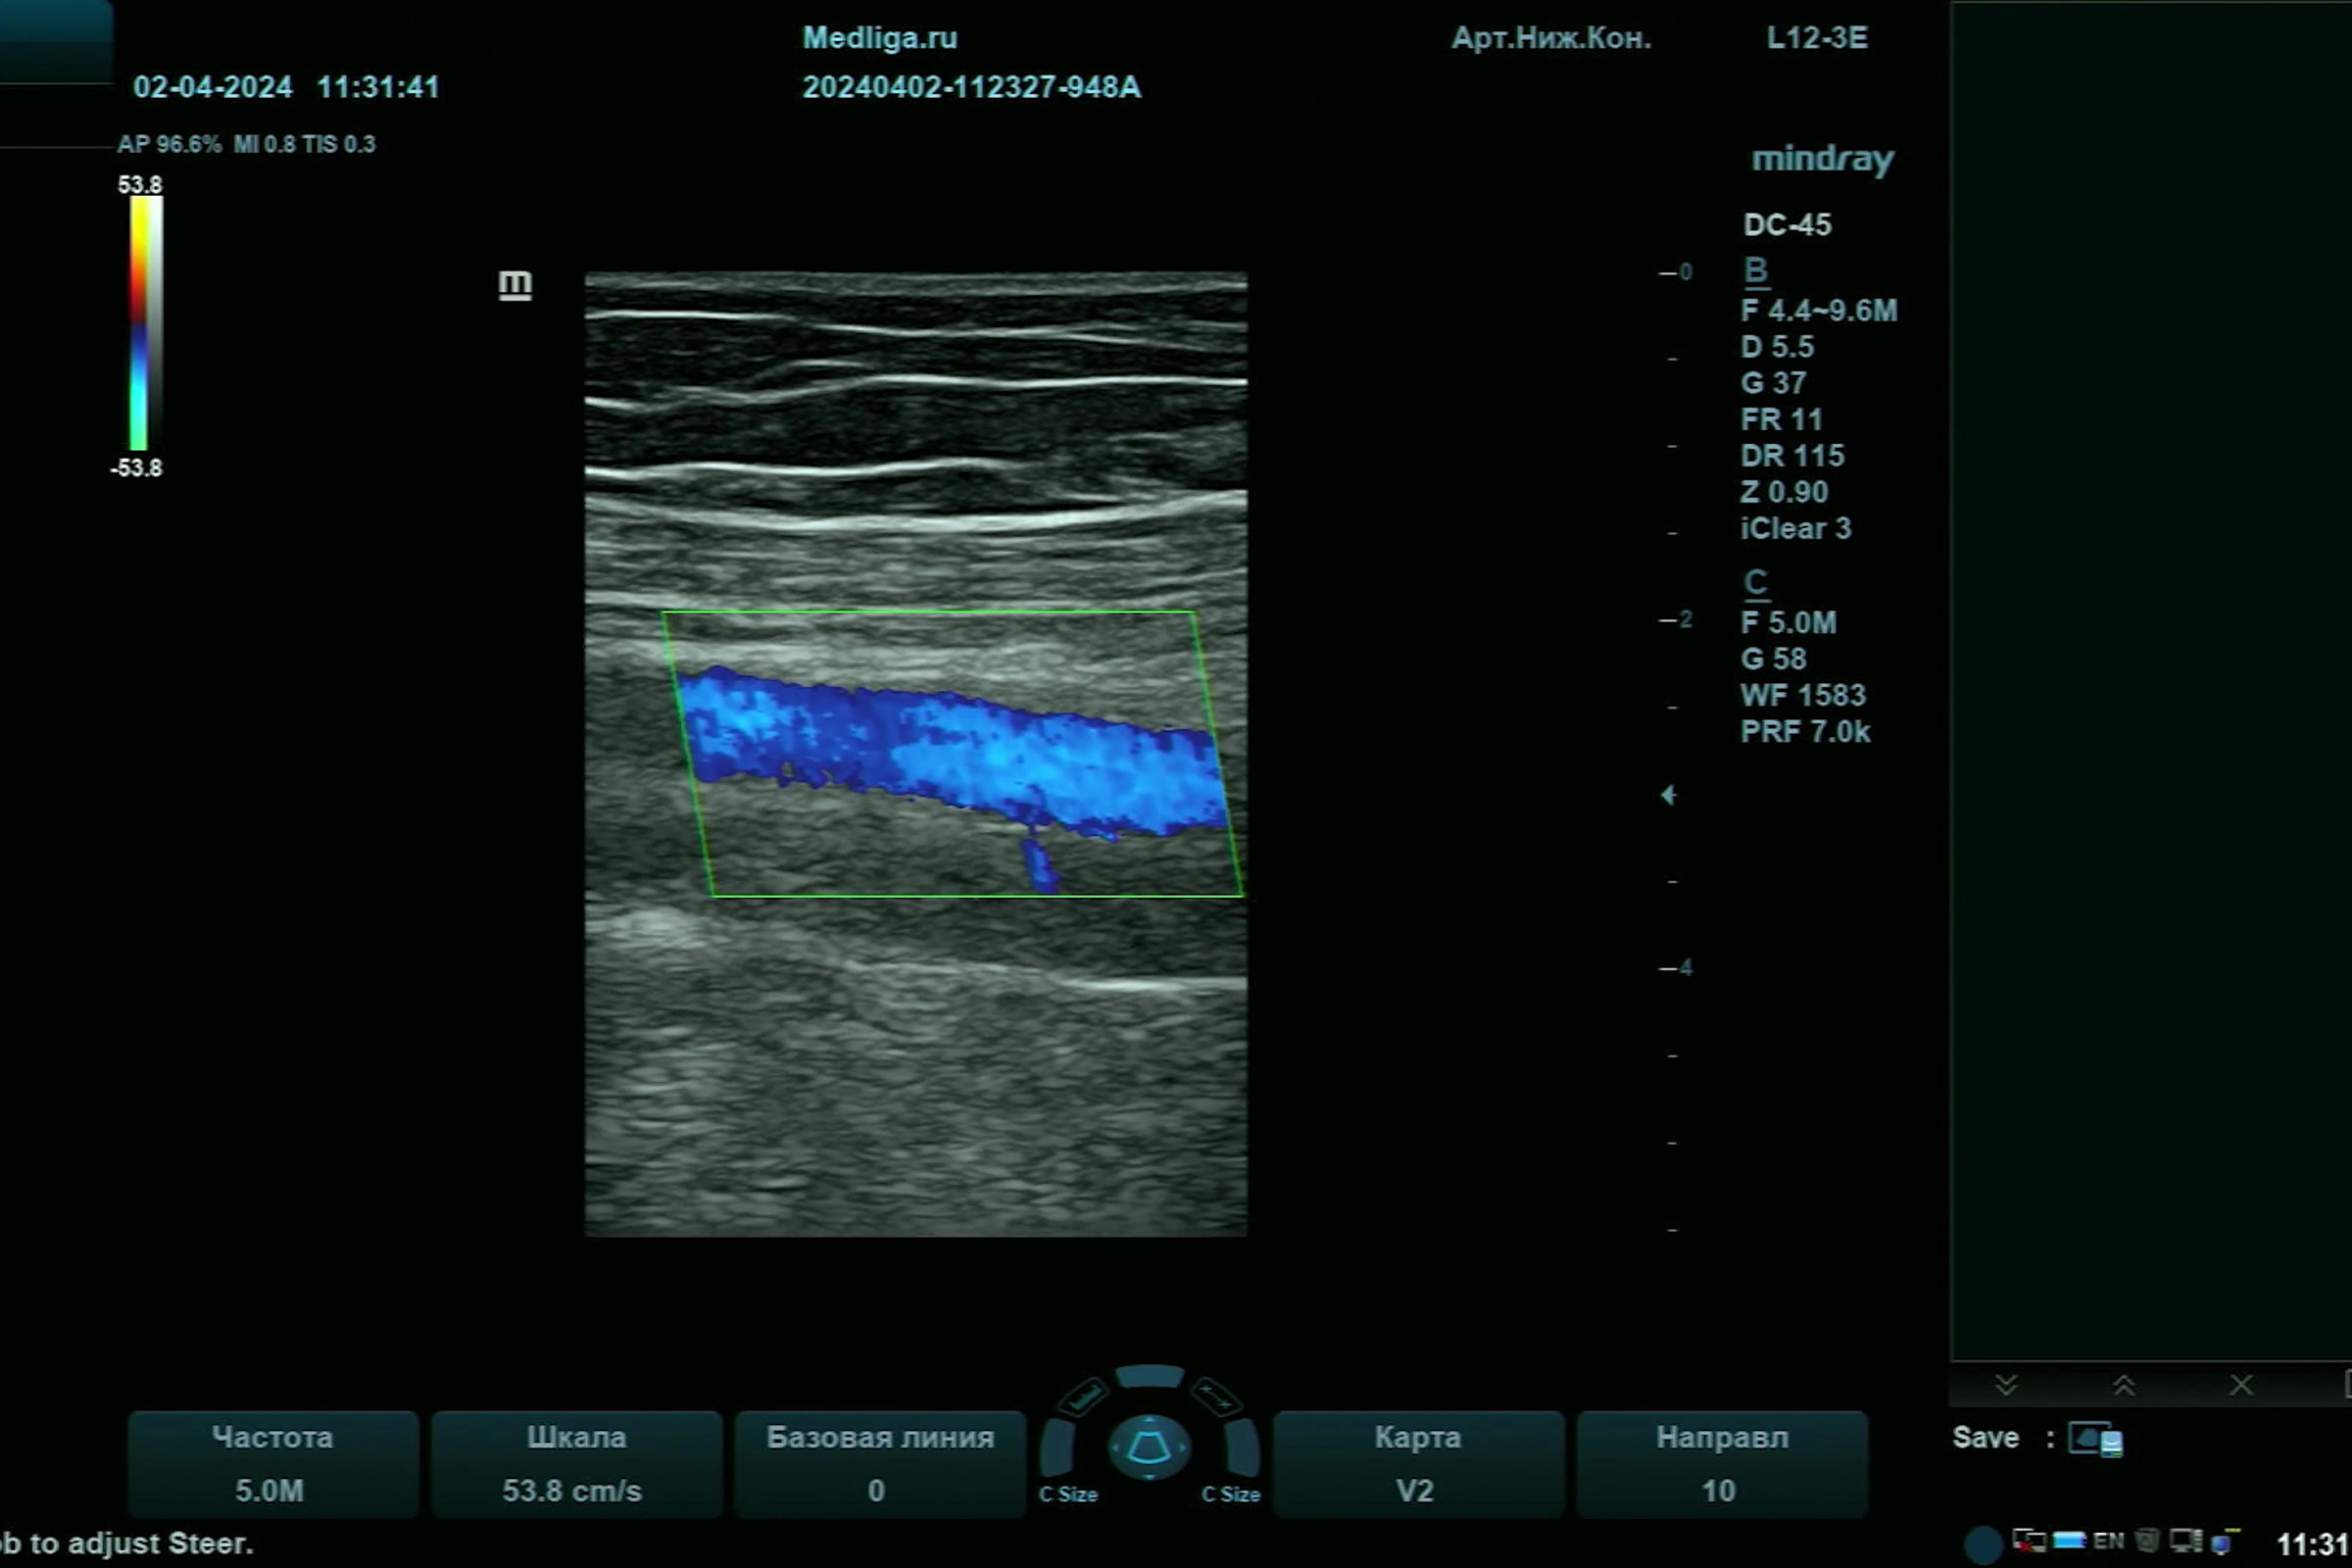

Видео узи артерий

Видео узи артерий 107 фото